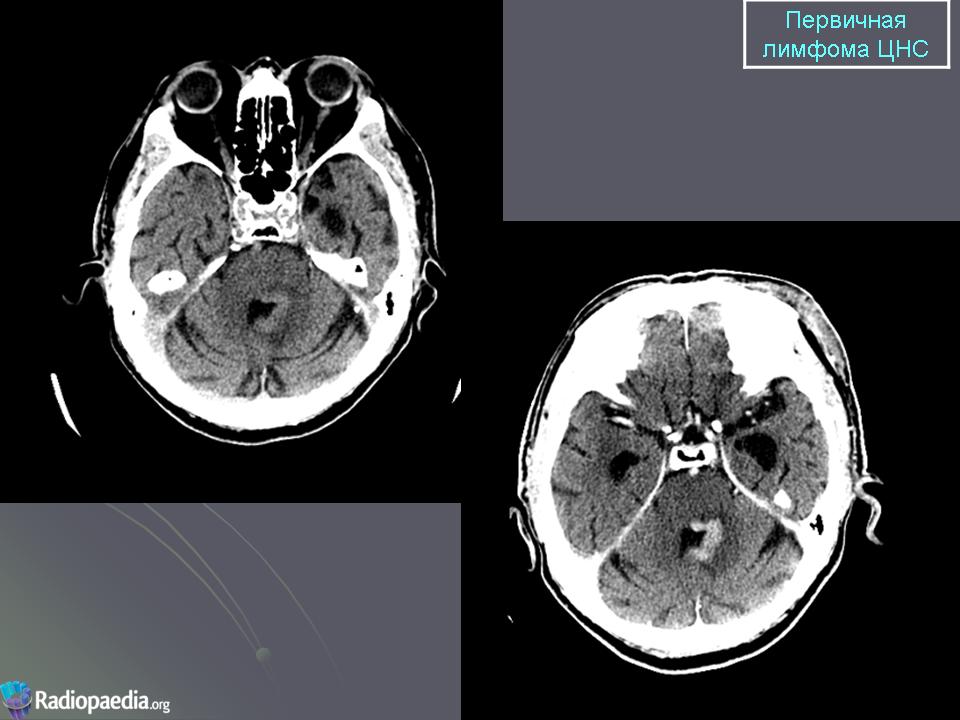

Первичные лимфомы ЦНС. Вс, 22/05/2011 - 21:45 #1 Катенёв Валенти... Не на сайте Был на сайте: 7 лет 5 месяцев назад Зарегистрирован: 22.03.2008 - 22:15 Публикации: 54876 Продолжение.Приложения:

Продолжение.